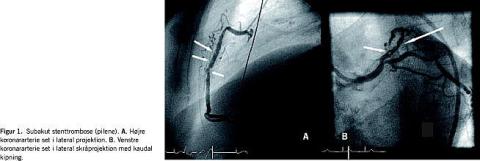

En 61-årig mand blev indlagt med AKS. Han havde erkendt PV, hypertension og artritis urica og havde tidligere haft mavesår. Han havde ikke tidligere haft tromboemboliske episoder, og hæmatologien havde været stabil over en årrække under behandling med hydroxyurea. Ved indlæggelse var hæmoglobin-B-, hæmatokrit- og trombocyttallene inden for normalområdet. Et elektrokardiogram (ekg) viste ingen signifikante forandringer og plasma (P)-kreatinkinase isoenzym MB (CK-MB)-fraktion og P-troponin T var ikke forhøjede. En ekkokardiografi viste en normaldimensioneret, velfungerende venstre ventrikel. Patienten blev behandlet med nitroglycerin, enoxaparin, aspirin og simvastatin, mens man primært undlod behandling med clopidogrel pga. forventet øget blødningsrisiko. Efterfølgende var hans tilstand ustabil i flere dage. En koronarangiografi viste nonsignifikant venstre hovedstammesygdom, okklusion af det andet segment af højre koronararterie (RCA) og stenose på første segment af ramus decendens anterior (LAD). Efter forbehandling med clopidogrel (300 mg efterfulgt af 75 mg i tre dage) blev der udført PCI med standarddosis ufraktioneret heparin (70 IU/kg legemsvægt) og implantation af en 4 × 18 mm almin-delig metalstent (Bx Sonic) i RCA og en 3 × 23 mm sirolimusafgivende stent (Cypher Select) i LAD. Begge stent blev implanteret ved 12 atmosfæres inflationstryk, og det afsluttende angiogram viste tilfredsstillende forhold og ingen tegn på koronardissektion, reststenose eller trombe. En kontrolundersøgelse med intrakoronar ultralyd var ikke tilgængelig. Proceduren varede en halv time, og blodstørkningstiden blev ikke målt undervejs. Ved procedureafslutning blev indførings-sheath i a. femoralis fjernet med en lukkeanordning, og der blev ikke givet protaminsulfat. To timer efter proceduren opstod der brystsmerter og ekg-forandringer, som svandt ved behandling med nitroglycerin, men otte timer efter første PCI fik patienten persisterende brystsmerter og forbigående ST-segment-elevationer. Akut koronar angiografi viste SST i begge de stentede koronarkar (Figur 1 ). Efter påbegyndelse af i.v. infusion med glykoproteinhæmmeren abciximab blev der foretaget re-PCI. Operatøren valgte at foretage fornyet stentimplantation på mistanke om subangiografisk dissektion ved stentkanterne. I RCA blev der distalt og proksimalt med overlapning til den første stent implanteret henholdsvis en 4 × 13 mm metalstent (Bx Sonic) og en 4 × 8 mm metalstent (Bx Sonic). I LAD blev der indsat en 3 × 28 mm sirolimus-afgivende stent (Cypher Select) med symmetrisk overlapning af den første stent. Begge stent blev postdilateret ved højt tryk (18 atmosfære) med nonkompliante PCI-balloner og et godt angiografisk resultat. Man gav enoxaparin i yderligere tre dage, og resten af forløbet var ukompliceret. Et ekg viste udvikling af negative T-takker i prækordialafledningerne og P-CK-MB steg til 27 μg/l, mens trombocyttallet i hele forløbet var under 500 × 109 /l. En ekkokardiografi ved udskrivelse viste let anteroseptal hypokinesi og venstre ventrikels uddrivningsfraktion var 50%. Den antitrombotiske behandling har siden været clopidogrel og aspirin, hvorpå patienten har været symptomfri i syv måneder.